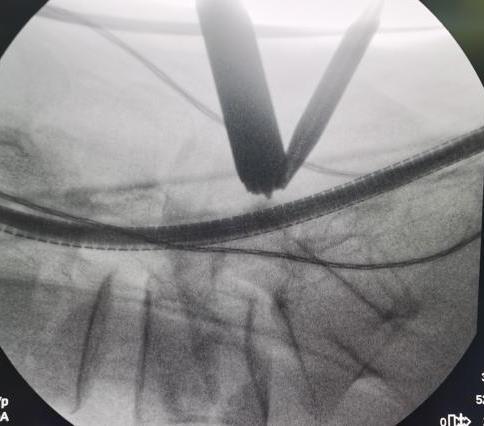

• 超声内镜引导下胃旁曲张静脉精准断流术治疗食管胃静脉曲张出血的疗效分析(附20例报告)

2025, 31(8):85-90. DOI: 10.12235/E20250036

摘要 (153) HTML (42) PDF 5.38 M (98) 评论 (0) 收藏

摘要:目的 探讨超声内镜引导下胃旁曲张静脉精准断流术治疗食管胃静脉曲张出血的疗效。方法 回顾性分析2024年1月1日-2024年12月31日于该院接受超声内镜引导下胃旁曲张静脉精准断流术治疗的20例肝硬化食管胃静脉曲张出血患者的临床资料,并评估治疗效果。结果 20例患者均顺利完成超声内镜引导下胃旁曲张静脉精准断流术;注射组织胶联合置入弹簧圈(16例)和单独注射组织胶(4例)均成功阻断胃旁来源的曲张静脉;所有患者均未发生穿孔、食管贲门狭窄、大出血、败血症和异位栓塞。1例单独注射组织胶的患者,术后胃旁曲张静脉少许渗血,经降低门静脉压力治疗3 d后好转,另1例单独注射组织胶患者,术后出现低热,抗感染3 d后体温恢复正常。结论 超声内镜引导下胃旁曲张静脉精准断流术治疗食管胃静脉曲张出血的临床疗效好,异位栓塞、大出血、感染和穿孔等并发症少,但仍需要密切随访,观察胃旁曲张静脉的排胶问题。